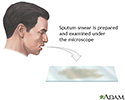

A sputum fungal smear is a laboratory test that looks for fungus in a sputum sample. Sputum is the material that comes up from air passages when you cough deeply.

A sputum sample is needed. You will be asked to cough deeply and spit any material that comes up from your lungs into a special container.

The sample is sent to a lab and examined under a microscope.